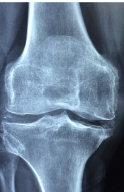

다리 관절에 좋은 음식 다리 관절에 좋은 운동 등 다리 관절 관련 정보 알아보도록 하겠습니다.다리 관절은 다리뼈와 골반뼈, 무릎, 발목, 발꿈치 등으로 이루어져 있습니다. 이들 관절은 서로 협력하여 우리 몸을 움직이는 데 중요한 역할을 합니다.

다리 관절은 일상생활에서 자주 사용되기 때문에 다양한 원인으로 손상될 수 있습니다. 만성적인 무리나 운동 부상, 골관절염 등이 그 예입니다. 이러한 손상으로 인해 다리 관절 통증, 감각 이상, 보행 장애 등이 발생할 수 있습니다.